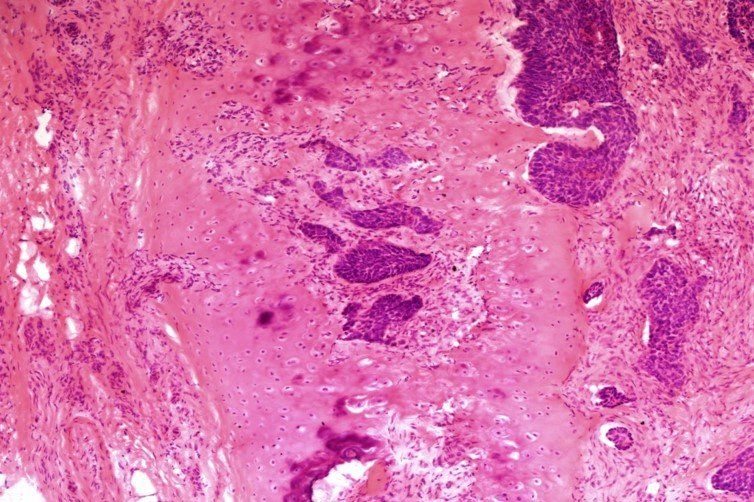

H E - Mohs-skema

Hier is 'n H E-skyfie wat die inval van basale selkarsinoom in kraakbeen wys vanaf weefsel wat van die neusbrug geneem is. Punte is afgetrek vir: Eosine-intensiteit te toutjies, mesmerke, voue en kreukels. Hierdie skyfie het 7/10 by die assessering behaal.